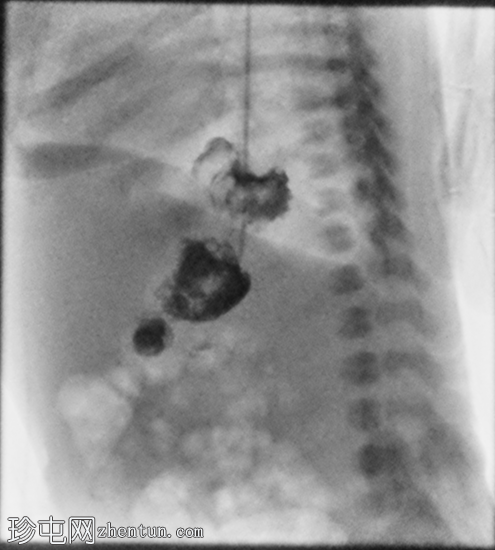

足月新生儿无法耐受任何喂养,经胃管/口服喂养后出现大量呕吐。评估是否存在肠旋转不良和胃排空障碍。

胃部初始显影,并立即反流至食管裂孔疝。在其近端可见管径正常的远端食管。十二指肠降部和横部显影较弱,左上腹可见数段管径较小/部分减压的近端小肠显影。

延迟1小时拍摄的X线片显示食管裂孔疝和胃部仍有造影剂残留,造影剂远端扩散受限,很可能是由于造影剂用量较少所致。充满气体的肠袢外观正常,乙状结肠内可见气体,直肠内未见气体。

这是一例儿童患者在透视下发现的食管裂孔疝病例。

最初的临床考虑是肠旋转不良,因为患者频繁且呕吐量大,但后来怀疑这是由中等大小的食管裂孔疝引起的。